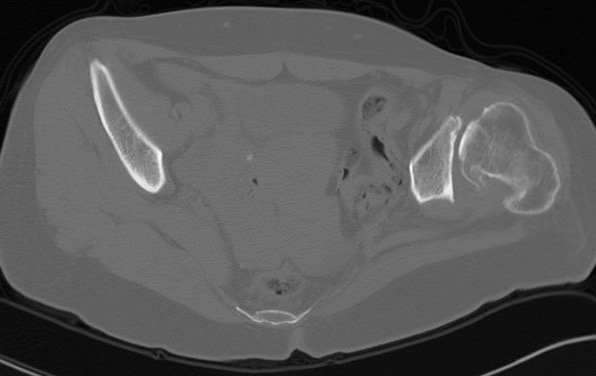

Crowe IV

Small femur - small femoral stem +/- modular - reduce excessive anteversion > 3- 4 cm LLD - shorten femur |

Crowe IV: Use normal acetabulum, shorten femur with subtrochanteric osteotomy + trochanteric slide